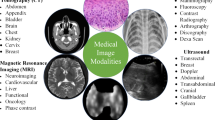

Loss of human lives can be prevented or the medical trauma experienced in an injury or a disease can be reduced through the timely diagnosis of medical anomalies. Medical anomalies include glaucoma, diabetic retinopathy, tumors [ 34 ], interstitial lung diseases [ 44 ], heart diseases and tuberculosis. Diagnosis and prognosis involve the understanding of the images of the affected area obtained using X-ray, magnetic resonance imaging (MRI), computed tomography (CT), positron emission tomography (PET), single photon emission computed tomography or ultrasound scanning. Image understanding involves the detection of anomalies, ascertaining their locations and borders, and estimating their sizes and severity. The scarce availability of human experts and their fatigue, high consultation charges and rough estimate procedures limit the effectiveness of image understanding. Further, shapes, locations and structures of the medical anomalies are highly variable [ 55 ]. This makes diagnosis difficult even for specialized physicians [ 4 ]. Therefore, human experts often feel a need for support tools to aid in precise understanding of medical images. This is the motivation for intelligent image understanding systems.

2 Medical image understanding

Medical imaging is necessary for the visualization of internal organs for the detection of abnormalities in their anatomy or functioning. Medical image capturing devices, such as X-ray, CT, MRI, PET and ultrasound scanners capture the anatomy or functioning of the internal organs and present them as images or videos. The images and videos must be understood for the accurate detection of anomalies or the diagnosis of functional abnormalities. If an abnormality is detected, then its exact location, size and shape must be determined. These tasks are traditionally performed by the trained physicians based on their judgment and experience. Intelligent healthcare systems aim to perform these tasks using intelligent medical image understanding. Medical image classification, segmentation, detection and localization are the important tasks in medical image understanding.

Medical Image Processing regards a set of methodologies that have been developed over recent years with the purpose of improving medical image quality, improving medical data visualization, understanding, and assisting medical diagnosis, and so on. Following past years tendency, it is foreseen that these methodologies will increase in complexity and will also have an increasing range of applications. In the last decade, the discipline has undergone a remarkable evolution, with the availability of large volumes of data and the increase in computational power. Deep learning is gaining protagonism and increasing relevance in the medical image processing field and has achieved great success over conventional techniques and is one of the most attractive areas in this field. Despite all the recent advances in medical image analysis in the last decades, there is still a significant uncharted territory and much to be understood in this field mainly due to the daily advances in medical imaging devices. Medical images are typically noisy images due low contrast-to-noise ratio and low spatial and temporal resolution. These characteristics introduce uncertainty in image analysis making it more difficult to quantify information content. Information theory provides theoretical background and tools to quantify information content, and uncertainty, in medical images. This Research Topic aims at presenting the latest advances in medical image processing methodologies and their contribution to the medical field and leveraging research on medical image processing. This Topic intends to cover the development and implementation of new medical image-based algorithms and strategies using biomedical image datasets. The overall aim of this Research Topic is to disclose scientific knowledge on medical image processing and its impacts on the community. This Research Topic welcomes research in the medical image analysis field and intents to promote the dissemination of new research results in the field of medical image processing. We welcome original papers that contribute to medical image understanding through new processing methodologies using image datasets from different medical imaging modalities such as (but not limited to): X-ray Ultrasonography Magnetic resonance (MRI) Computed tomography (CT) Nuclear medicine (PET; SPECT)